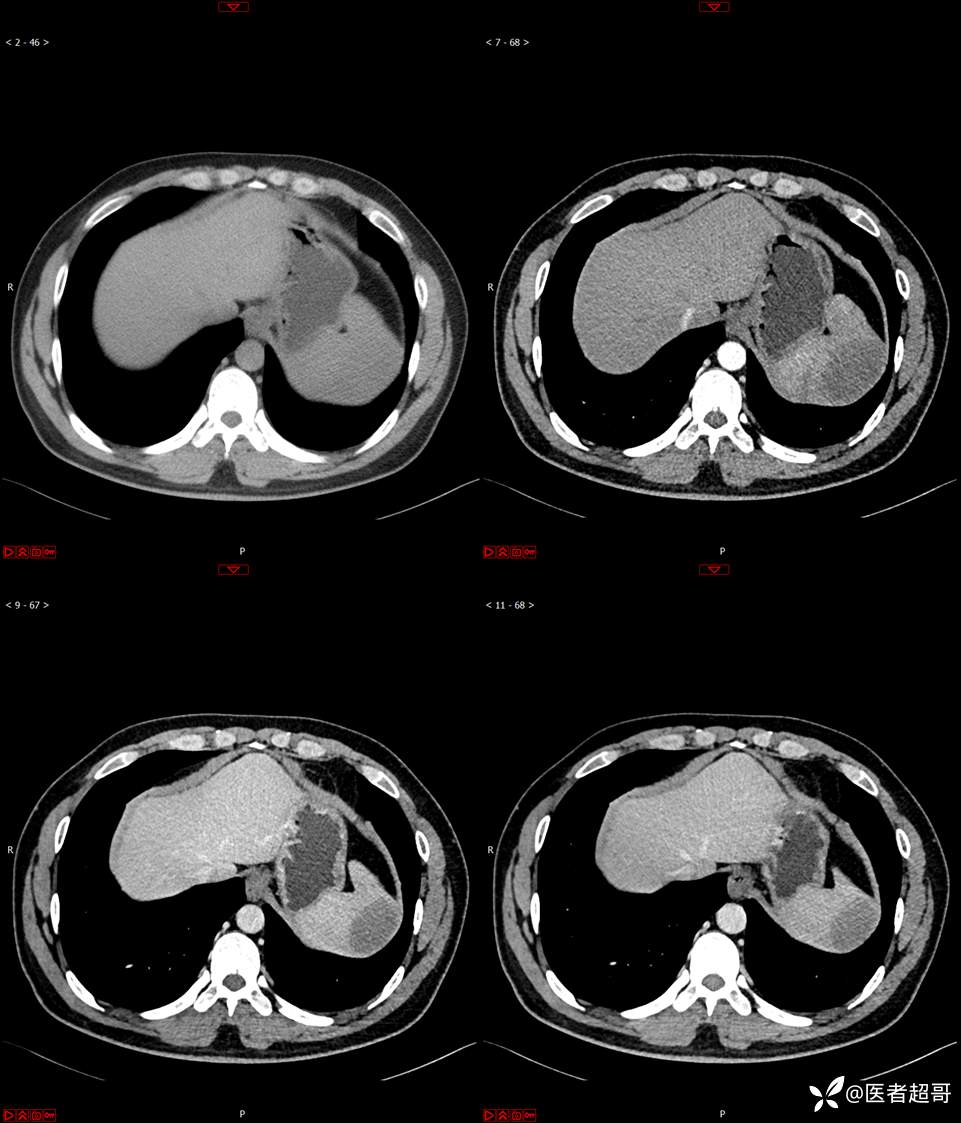

【影诊笔记596】脾脏占位01,你的病谱能网住吗?请分析,留言查询病理及术程!

主 诉:发现脾占位2月余。

现病史:患者2月余前体检彩超提示脾占位性病变,未予特殊诊治,2023.12.1于潍坊市坊子区人民医院行肝胆胰脾MR平扫提示脾脏占位性病变,左肾小囊肿,现患者无腹胀、腹泻,无恶心呕吐,无胸闷憋气等症状,今为求进一步治疗,患者来我院就诊,门诊以“脾占位性病变”收入院。患者自发病以来,一般情况可,神志清,精神可,饮食、二便正常,睡眠可,体重体力无明显改变。